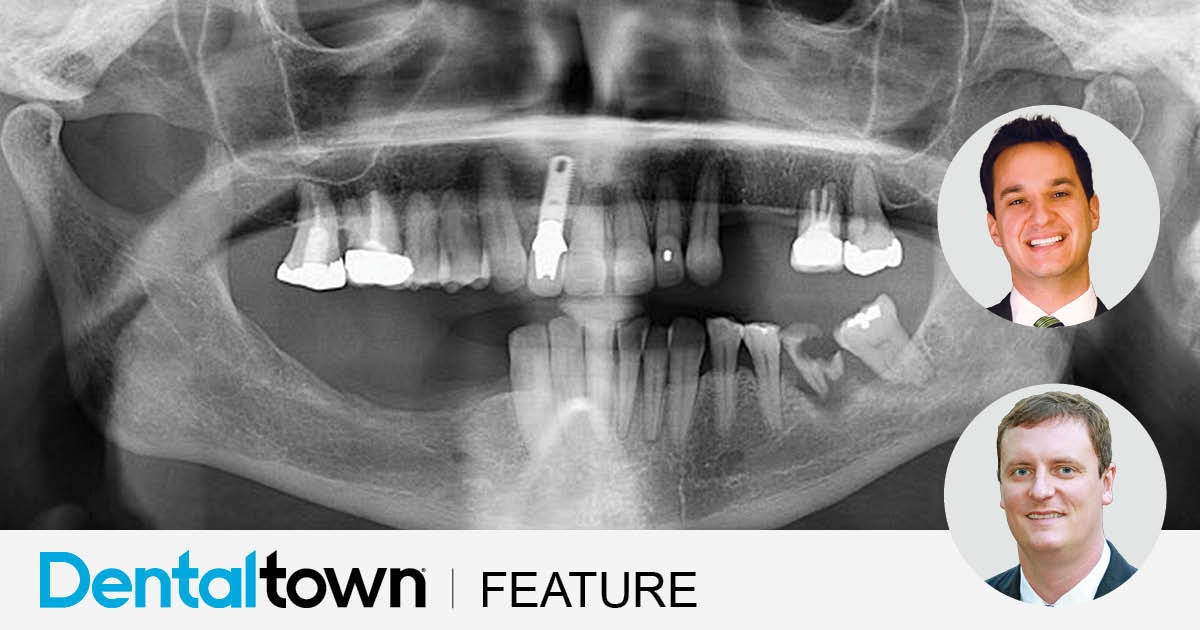

A failed implant nearly derailed this full-arch case from Drs. Danny Domingue and Cory Glenn—until a digital workflow and pterygoid rescue saved the smile and exceeded patient expectations

by Drs. Danny Domingue and Cory Glenn

June 2025